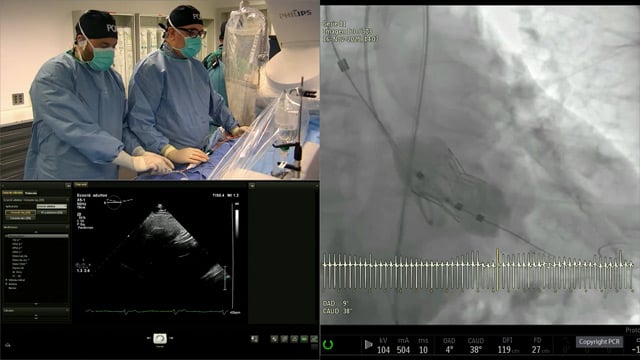

Managing TAVI-embolisation device

22 May 2025 – From EuroPCR 2025

Focus on managing TAVI device embolization in this specialized session. Discuss detailed techniques such as TAVI-in-TAVI procedures, addressing valve dysfunction, and innovative balloon-assisted retrieval methods for migrated transcatheter heart valves, emphasizing procedural nuances and bailout strategies.